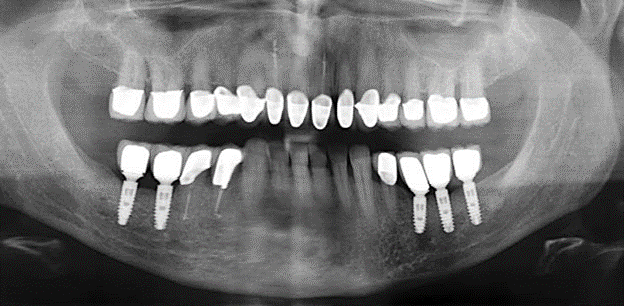

The ten-year check-up revealed no indications of advancing clinical attachment loss or peri-implant bone substance loss (Fig. 3).

Standardised and regular risk-adapted care in the scope of SPT is the key to treatment success for the clinical long-term success in periodontically compromised patients. This is particularly true for patients fitted with implants following successfully completed periodontal treatment (Fig. 11a and b).